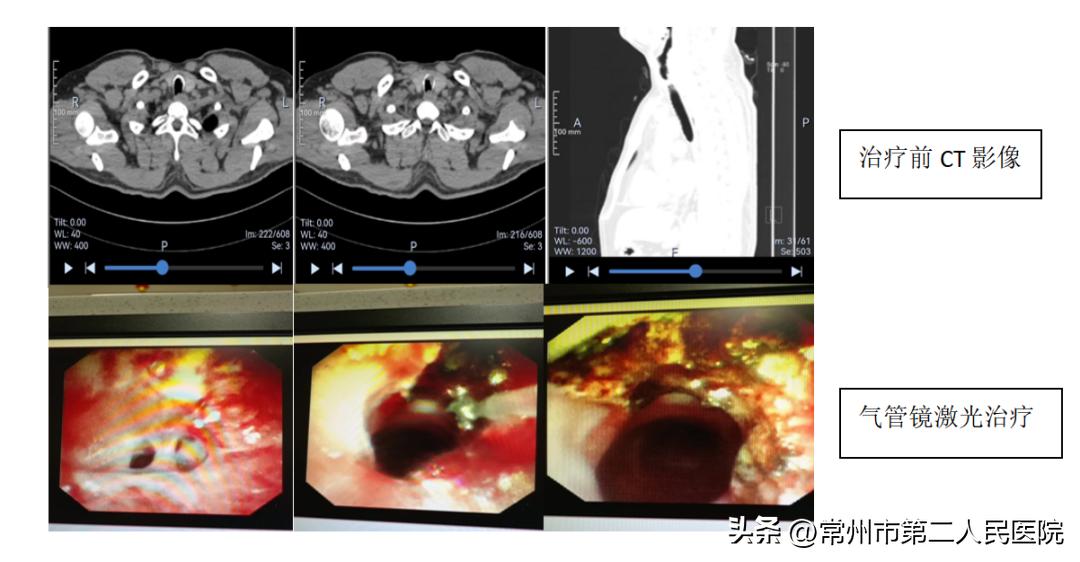

“我们仔细分析了张某外院带来的肺部CT,发现他的气管上段与正常的情况不一样,详细查体后发觉他气喘的声音主要在气管上段,喘鸣音沿着大气道传导,肺部的哮鸣音也不是很典型;而常见的过敏性哮喘,是小气道疾病,哮鸣音通常在肺部为主。我们立即让他检查了肺部气管的三维CT重建,结果显示气管上段有异常狭窄。随即再急诊安排呼吸病介入诊疗中心气管镜检查,这才发现了真正的问题所在。原来,张某声门下腔气管上段严重的疤痕狭窄、部分呈膜状分隔气管。这意味着,如果张某继续按照重症支气管哮喘治疗,气管将会完全堵死,严重的会出现突发性窒息,后果不堪设想。”常州市第二人民医院呼吸病介入诊疗中心主任医师杨明夏介绍道。

经过充分沟通后,常州二院呼吸病介入诊疗中心团队紧急为张某予以气管镜下激光消融切除膜状异常结构、疤痕消融,并给予局部冷冻处理、气管球囊扩张塑形气管,气管狭窄一下子解除,管腔通畅。